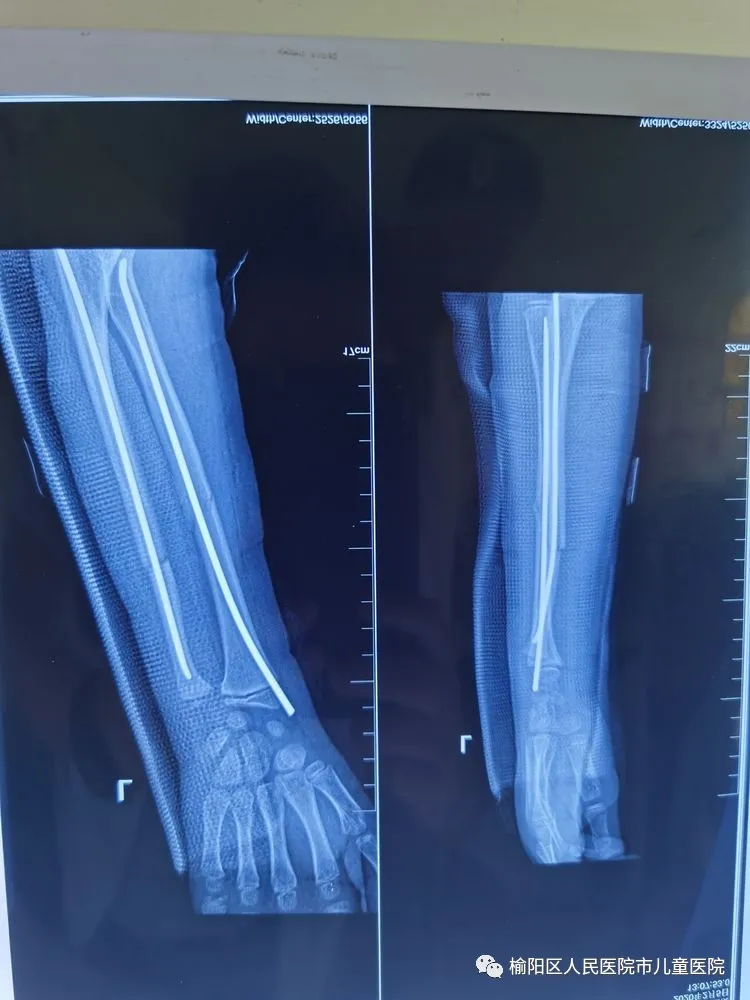

術(shù)后5個月,完美愈合。

彈性髄內(nèi)針治療小兒四肢骨折優(yōu)點:手術(shù)時間短,創(chuàng)傷小,住院時間短,骨折愈合快,費用低。